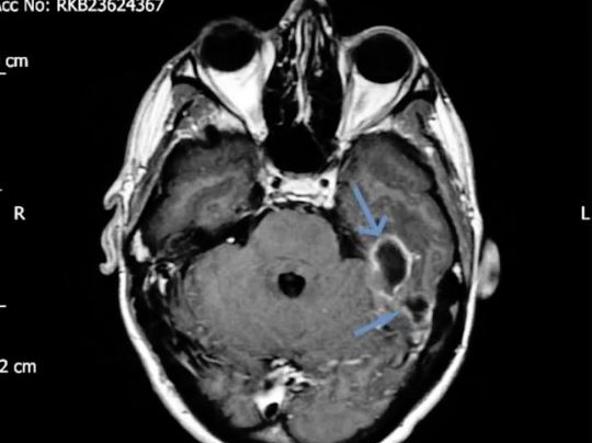

31-vjeçari u shtrua me urgjencë në spitalin e Coventry, ku bëri rezonancë, skaner dhe kontrolle të detajuara, deri sa u bë zbulimi i rëndë, shkruan noa.al.

Kështu ai iu nënshtrua një ndërhyrje kirurgjikale gjatë së cilës iu hoq një pjesë e shkopit, e cila mendohet se kishte vite e bllokuar dhe për pasojë, i shkaktonte probleme.